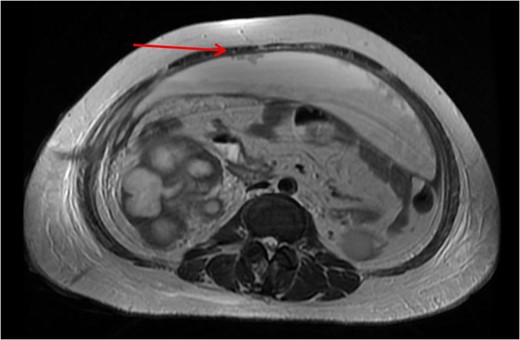

Xanthogranulomatous pyelonephritis (XGPN) is a rare form of chronic pyelonephritis with progressive loss of renal function. Commonly, obstructing urinary calculi are seen. It is difficult to differentiate between XGPN and malignancy in many cases, and the diagnosis is usually only confirmed post-operatively upon histopathological examination of the specimen. Surgical treatment is often the main treatment modality due to suspicion for malignancy. Here, we present a case of XGPN that presented with abdominal distension, which was eventually discovered to be due to a preperitoneal abscess.

She underwent insertion of a right percutaneous nephrostomy drain, percutaneous drainage of the anterior abdominal collection, as well as a percutaneous biopsy of the right renal soft tissue lesion. Urine cultures from the percutaneous nephrostomy grew Proteus mirabilis. Fluid cytology from the abdominal collection showed acute inflammatory cells. Biopsy of the renal lesion showed xanthogranulomatous inflammation.

After a period of antibiotic treatment, she underwent open right nephroureterectomy with exploration, drainage and washout of the preperitoneal collection. During surgery, 1 l of pus was drained from the preperitoneal space, and cultures grew P. mirabilis. The ureter was ligated below the level of the calculus and removed together with the kidney. Final histopathology results showed XGPN with no evidence of malignancy in the kidney or peritoneal lining.

Our patient had an atypical presentation with abdominal distension and presumed ascites, which was eventually revealed to be an anterior preperitoneal collection secondary to infection. Although the initial suspicion was that of a malignant process complicated by ascites, subsequent cytology and histopathological results showed that it was likely benign. In view of the non-functioning renal unit and significant abdominal collection, she underwent definitive surgery.

The most common urinary pathogen identified was Escherichiacoli [3], and common areas of involvement were the retroperitoneum and psoas muscle. In our patient, the retroperitoneal space was surprisingly not greatly involved, but rather it was the anterior preperitoneal space that had significant adhesions and inflammation. The pathogen identified from both nephrostomy and preperitoneal collection was P. mirabilis, showing that both pathologies were linked.